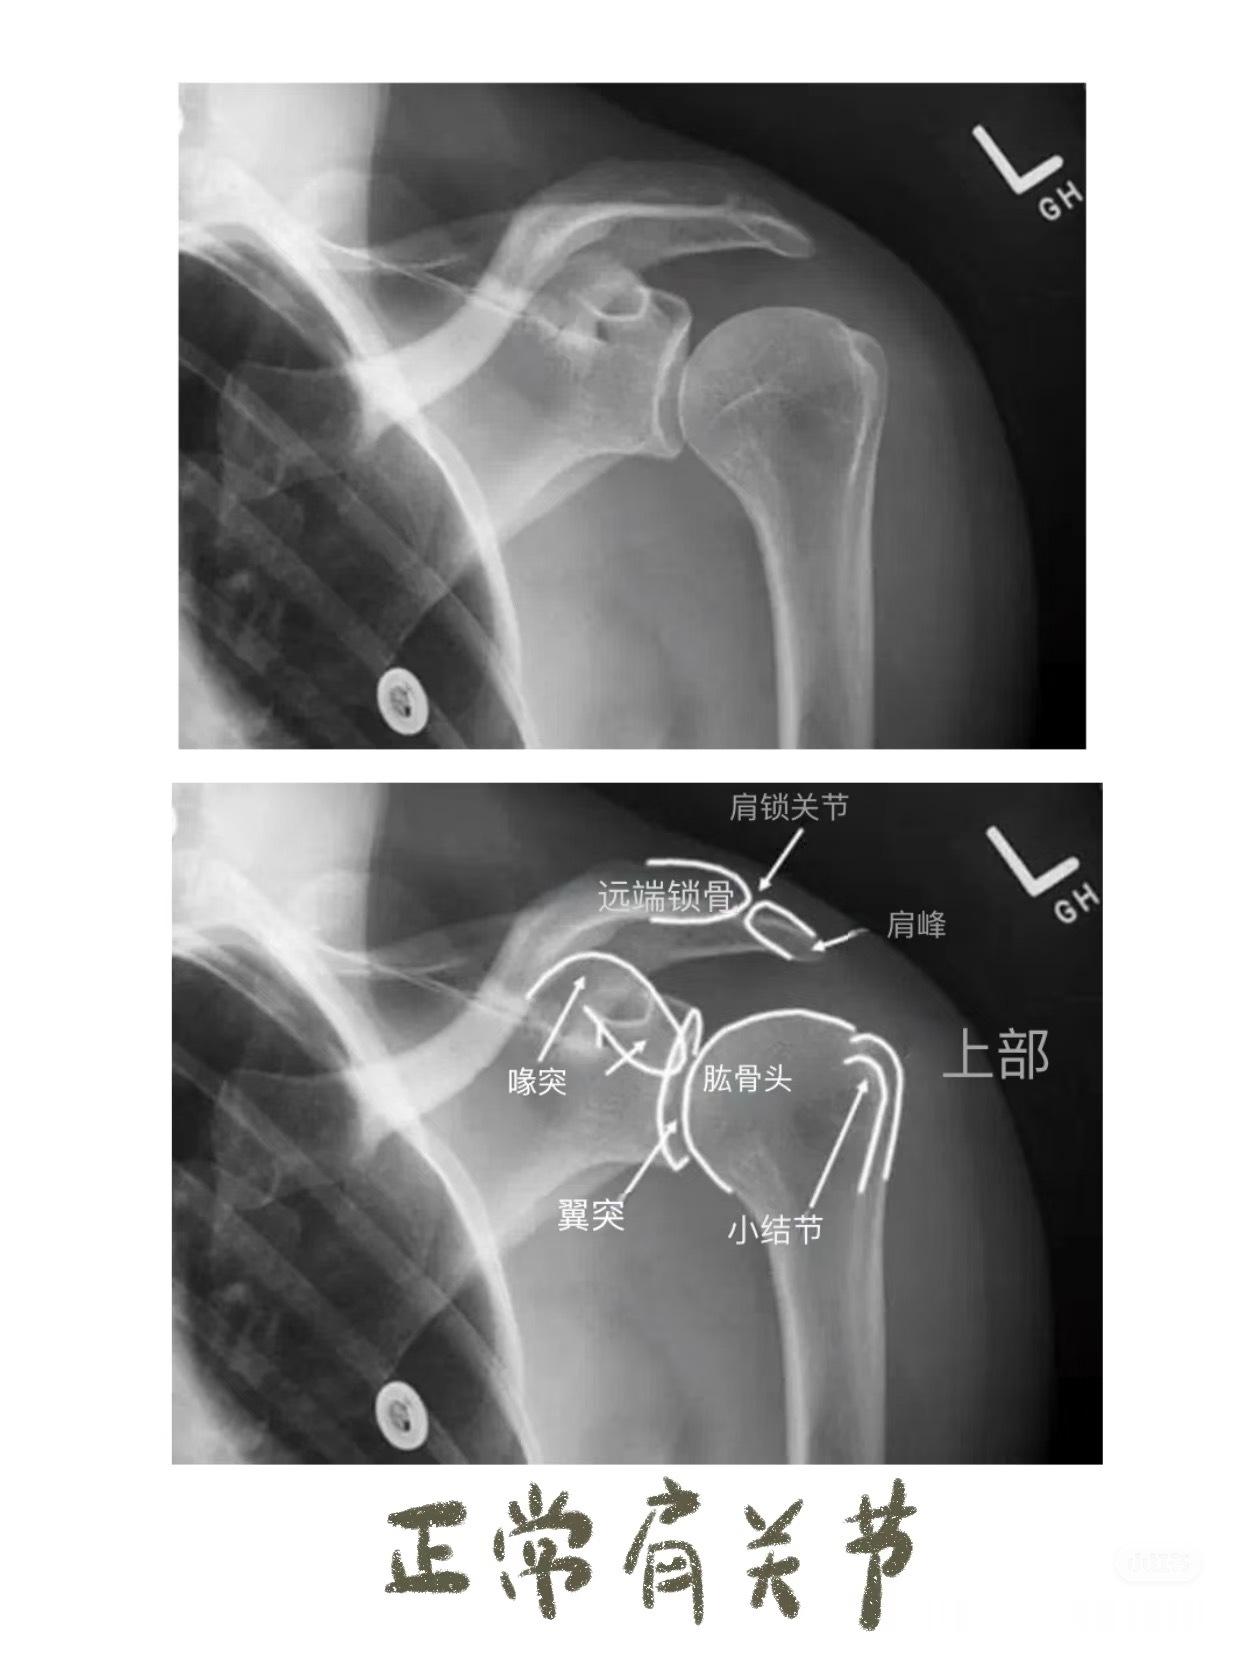

之前讲到影像学片子,膝盖和腰椎比较多,今天说些比较小众的——锁骨骨折,肘关节脱位,手部损伤等等👇🏻👇🏻【锁骨骨折的典型症状】01.疼痛与压痛——骨折部位出现持续性或阵发性剧烈疼痛。02.肿胀与皮下瘀斑——骨折后局部软组织损伤和出血,导致肿胀迅速出现,可能伴随皮下瘀血或青紫。03.畸形与异常活动——锁骨缩短、成角或旋转畸形,如骨折端上翘、隆起或凹陷。04. 活动受限——上肢抬举、伸展等功能受限,肩关节活动时疼痛加剧,甚至完全无法活动。05. 骨擦音/骨擦感——骨折断端摩擦时可触及异常活动或听到骨擦音,是骨折的典型体征。【肘关节脱位】01. 关节畸形——后脱位(最常见):尺骨鹰嘴向后突出,肘前窝饱满,前臂外观缩短,呈“靴状畸形”。——侧方脱位:肘关节向内或向外偏斜,形成肘内/外翻畸形。02. 肘后三角关系破坏 ——正常肘关节屈曲时,肱骨内/外上髁与尺骨鹰嘴构成等腰三角形;伸直时三点成一直线。——脱位后此关系完全失常。03. 弹性固定 ——关节被周围紧张韧带“锁扣”于半屈位,被动活动时有弹簧样阻力感。04. 骨性标志异常 ——后脱位时可触及肘后空虚感,尺骨鹰嘴异常隆起;——前脱位可触及肱骨远端。【手部骨折】拳击手骨折——握拳撞击——通常发生在第五掌骨(cr.骨科小龙笔记)大家如果还有关于骨折或者其他身体损伤的问题,都可以下方留言讨论